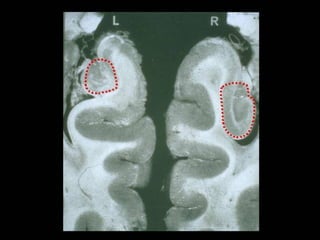

Hippocampal T2 signal changes

Hippocampal T2 signalchanges after prolonged febrile seizures

High-Resolution Hippocampal Imaging HHR Structural(voxel size = .4 x .4 x 3mm) HHR Functional EPI (voxel size = 1.6 x 1.6 x 3 mm)

High-resolution MRI ofthe MTL (Zeineh, Engel, Thompson, Bookheimer Neuroimage, 2001) (Ekstrom, Bazih, Suthana, Al-Hakim, Ogura, Zeineh, Burggren, Bookheimer. Neuroimag, 2009)